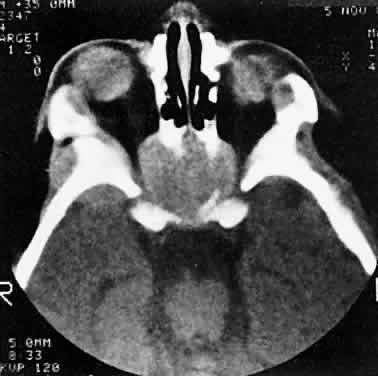

In dacryoadenitis, external inflammatory signs are localized to the superotemporal quadrant, and CT shows enlargement of the lacrimal gland (Fig. 24). Lacrimal gland inflammation may be bacterial, viral, or a variant of IIPT. It is possible, however, that many cases of “idiopathic” dacryoadenitis represent unidentified viral infections. In bacterial dacryoadenitis, a leukocytosis with a left shift may be present.96 In questionable cases, a 1-week course of oral antibiotics can be administered to these patients. Among children, the probability that an enlarged lacrimal gland represents neoplasia rather than inflammation is lower than among adults, although epithelial lacrimal gland tumors occasionally may occur in the pediatric population and can produce external inflammatory signs. If the general signs and symptoms of IIPT are lacking, a biopsy should be performed.

Fig. 24. A. Nonbacterial dacryoadenitis may be unilateral or bilateral. External inflammatory signs are maximal in the superotemporal quadrant. B. The left lacrimal gland is enlarged, with a shape molded by the globe and orbital walls. A neoplasm usually can be ruled out by analysis of the history, CT findings, and echographic characteristics, but a biopsy may be required in equivocal cases.